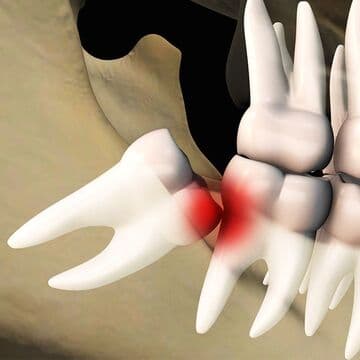

- 隣の歯(第二大臼歯)への悪影響

- 斜めや横向きに生えてくる親知らずは、隣接する歯との間にプラークが停滞することで、虫歯や歯周病の原因となります。

状態が悪い場合は、隣接する歯と親知らずの2本の抜歯が必要なるケースがあります。 - 歯肉の腫れや炎症(智歯周囲炎)